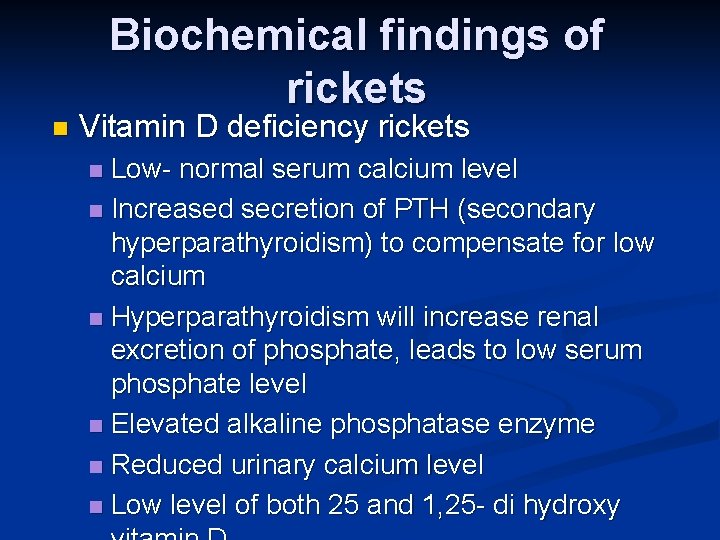

Biochemical findings of rickets n Vitamin D deficiency rickets Low- normal serum calcium level n Increased secretion of PTH (secondary hyperparathyroidism) to compensate for low calcium n Hyperparathyroidism will increase renal excretion of phosphate, leads to low serum phosphate level n Elevated alkaline phosphatase enzyme n Reduced urinary calcium level n Low level of both 25 and 1, 25 - di hydroxy n